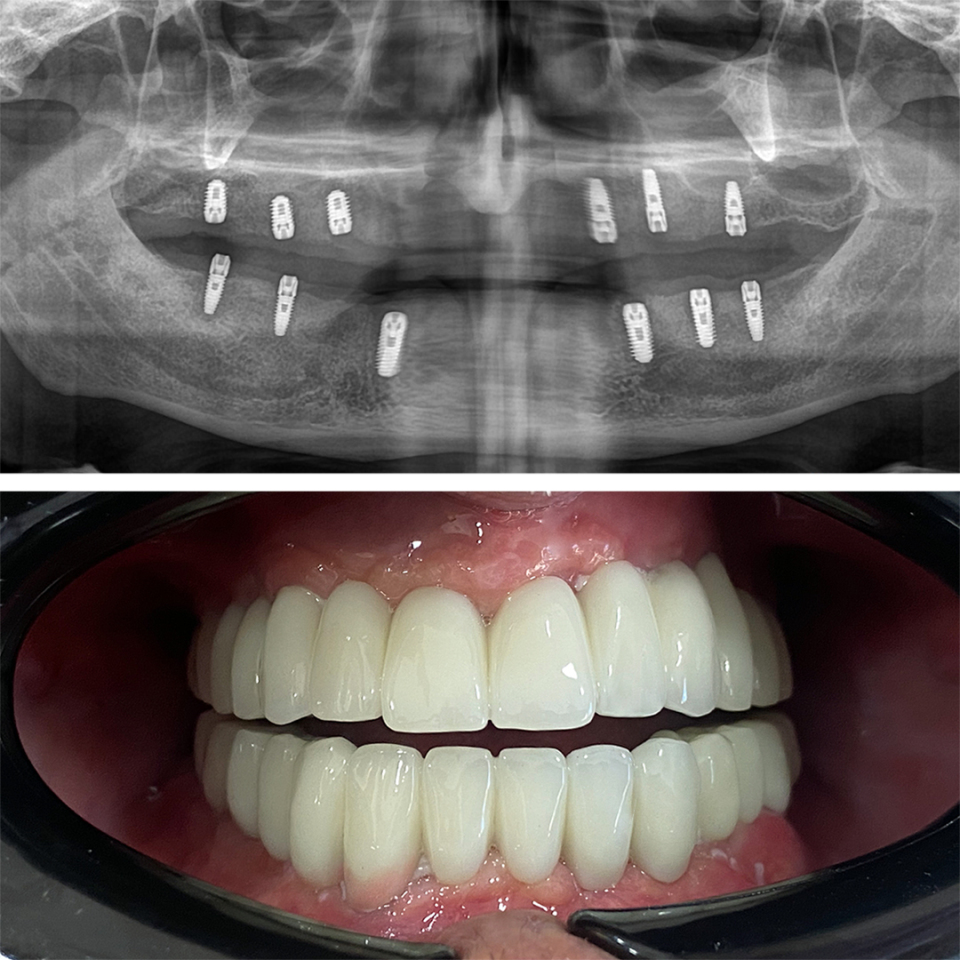

Smile Dental Clinic Turkey Gallery

Our Gallery and Happy Patients

Let’s make a change and put a perfect smile on your face with our dental clinic in Antalya/TURKEY.